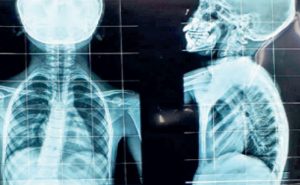

रीढ़ में विकृति आने को ही स्कोलियोसिस कहते हैं. सामान्य रीढ़ की हड्डी पीछे से देखने पर सीधी नजर आती है, जबकि स्कोलियोसिस में हड्डी में तीन तरीके से वक्र बने होते हैं.